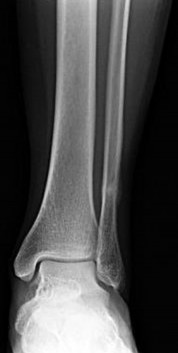

Question 1:

A 6-year-old child falls onto an outstretched hand resulting in the injury shown. Which nerve is most commonly injured in extension-type supracondylar humerus fractures with posteromedial displacement of the distal fragment?

Correct Answer: Radial nerve

Explanation:

In extension-type supracondylar fractures, the distal fragment displaces posteriorly. If it displaces posteromedially, the proximal fragment's sharp metaphysis is driven anterolaterally, thereby placing the radial nerve at the highest risk of injury. Conversely, posterolateral displacement of the distal fragment drives the proximal spike anteromedially, putting the median nerve (specifically the AIN) and brachial artery at risk.